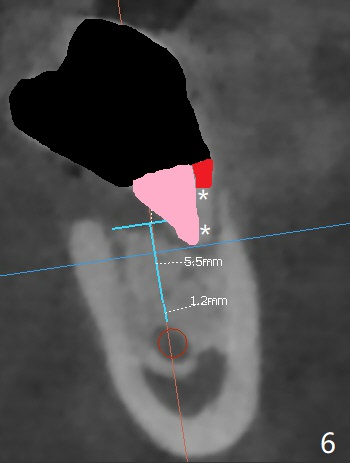

A 44-year-old woman has severe chronic periodontitis. The tooth #18 is nonsalvageable (Fig.1). To avoid distal end guide, do not remove the 3rd molar in the lab. While a 5x7.3 mm implant is long for the site (Fig.2), a 5.5x5.5 mm one seems to be a better option (Fig.3). The latter could be 1 mm more coronal. The last drill (5.0 mm) and cortical tap will be used free hand. #17 will be extracted after implantation. Since the patient is reluctant to have #16 to be extracted, place #18 implant ~ 1-2 mm more distal so that the implant crown will have some occlusal contact with #16. Prepare IS extra wide kit. Or use a 8/7 mm trephine bur to harvest cortical bone from the ramus. Drill a hole for fixation screw before removing the onlay graft. Keep the 3rd molar if possible. Prepare Tatum spacers to measure the size of #18 socket opening. In fact, the lab is able to place a 5x7.3 mm implant with 2 thread exposure buccal. Prepare sticky bone and PRFx2 to prevent periimplantitis. Soak one O-ring in case of having to extend osteotomy by .5 mm (next longer drill (1.5 mm) - 1 mm (O-ring)). For socket shield at #18 (Fig.6 *), section the tooth horizontal with a new surgical fissure bur (Fig.4 black area), use an end-cutting bur to remove buccal edge of the root (Fig.5 red area) and finally remove the lingual portion of the root (Fig.6 pink). Insert 4.5x10 mm dummy implant to determine whether the final implant 5x7.3 mm (bottom of the 1st line) will probably contact the shield. Buccal view of the lingually inclined 2nd molar (Fig.7). After removal of the crown of the 2nd molar (Fig.8 occlusal view), the lingual portion of the root is resected (Fig.9 black area). CT coronal sections show socket shield formation (Fig.10,11).

Lower Molar Immediate Implant, Prevent Molar Periimplantitis (Protocols, Table), Trajectory II, No Antibiotic Xin Wei, DDS, PhD, MS 1st edition 08/30/2019, last revision 02/02/2020